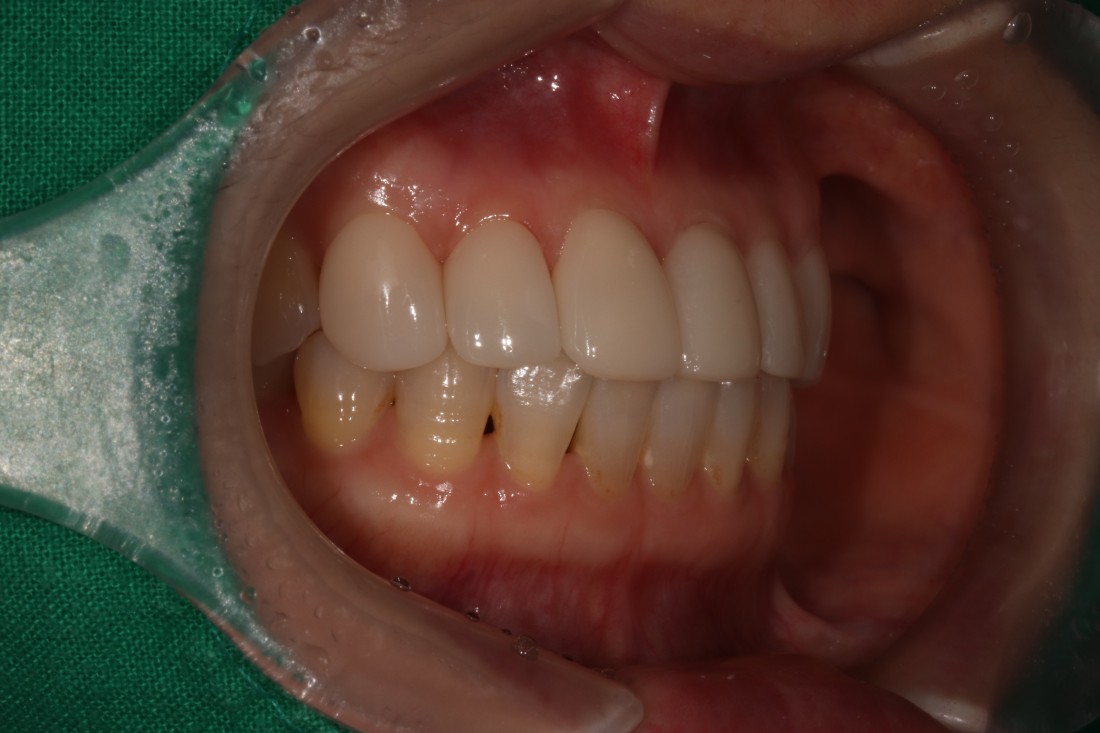

광주 무삭제 라미네이트 치과는

모든 분들에게 똑같은 진료를 권하는 것이 아닌,

개인별로 최적의 치료계획을 세워서

분과별 전문의 협진으로

최상의 치료결과를 만들어냅니다.

전문의 라미네이트 진료 뿐만 아니라

구강외과 전문의 임플란트,

구강내과 전문의 턱관절진료,

치아교정과 전문의 교정진료 등

다양한 치료방법을 조합하여

개인별로 최적의 치료계획을 통해

내 구강 구조에 제일 잘 맞는

치료법을 제시하고 있습니다.